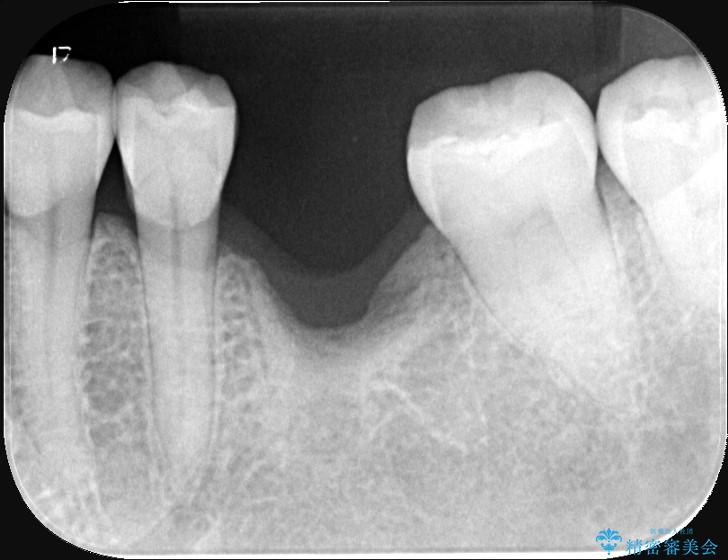

左下奥歯の抜歯後、長期間放置していたために、周囲の骨が吸収してしまいました。 特に垂直的な高さが不足しており、通常の術式ではインプラント埋入が難しい状態でした。

精密検査の結果、高さに制限はあるが厚みは十分に確保されていることが確認されました。